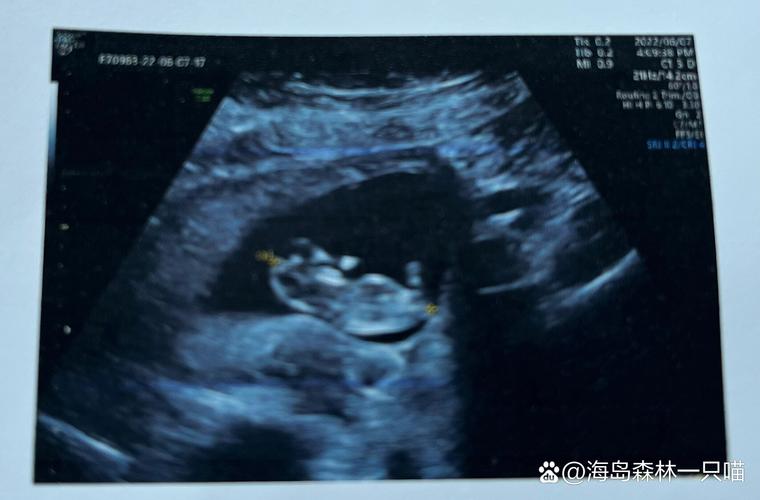

- 顶臀长(从头顶到臀部): 约 4 - 6.1 厘米。

- “人形”越来越明显: 胎儿不再像个“小海马”,头部占身体比例较大,但已经开始伸直,身体比例也在逐渐协调。

- 心脏: 心脏已经完全发育,并且有节奏地跳动,您可以通过多普勒仪器听到它强有力的心跳声(通常在110-160次/分钟)。

- 产检安排: 通常在11-14周之间,医生会安排第一次重要的排畸检查——NT(颈项透明层)检查,结合早期的抽血结果(唐筛),可以初步评估胎儿患有唐氏综合征等染色体异常的风险,请记得提前预约。